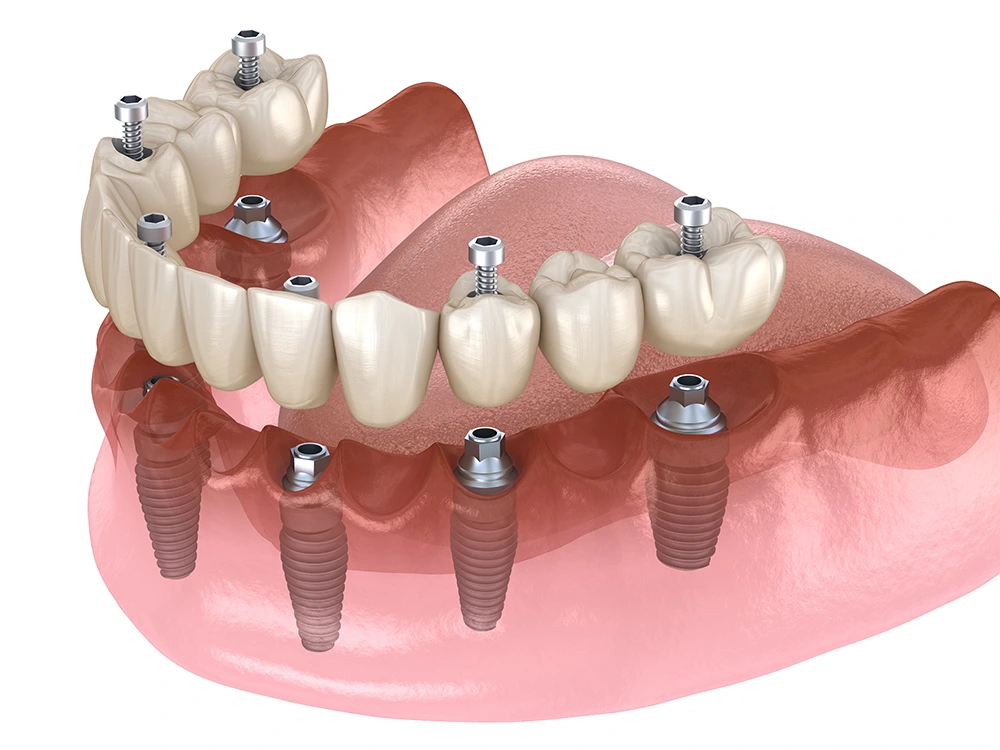

Implantodontia

O que é implante dentário?

Consiste em reconstruir um ou mais dente(s) perdido(s) através da implantação cirúgica de "pinos" no osso da maxila ou mandíbula. Esses "pinos" são os implantes de titânio. Os implantes dentários atuam como as raízes dos dentes perdidos. Um material biocompatível (não sofre rejeição) com nosso organismo. Posteriormente sobre os implantes dentários é instalada uma peça protética.

Indicação:

• Indicado para substituir:

• 1 dente perdido;

• Vários dentes ausentes;

• Pessoas que não se acostumam com dentaduras ou peças móveis.

• Observar antes se a pessoa é apta a receber implantes dentários. Isso na consulta será analisado.

• Trabalhamos com Prof. e Dr. Guilherme Carrilho.